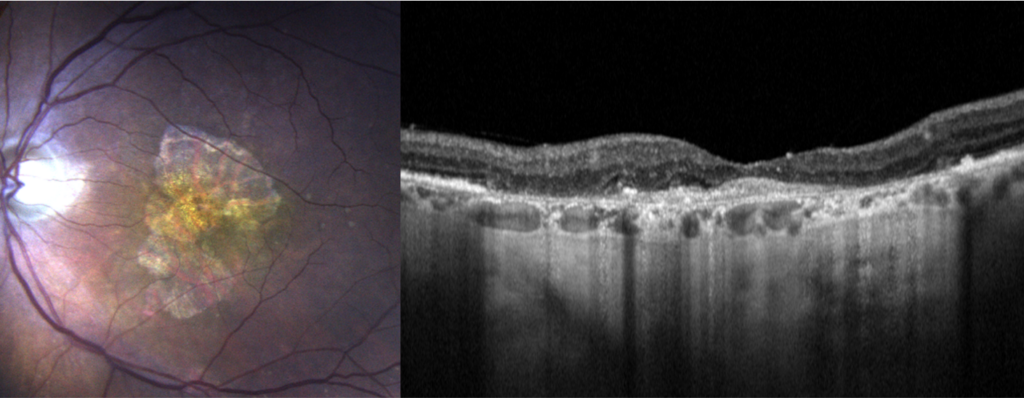

Lors du bilan, l’acuité visuelle est mesurée par l’orthoptiste. Ensuite un OCT maculaire permet de mesurer l’épaisseur de la macula et scanner la rétine à la recherche de signe d’atrophie. Une photo de l’aire maculaire est prise en couleurs et en auto fluorescence. Ce filtre met en évidence le nombre et l’étendu des plages d’atrophies. En cas de doute, sur une forme « humide » ces examens seront complétés par le module OCT Angiographique  (OCT-A) pour éliminer la présence de néovaisseaux. Ces mesures servent au diagnostique mais aussi à la surveillance de la DMLA.

Rétinophoto couleurs et autofluorescente avec plage d’atrophie géographique maculaire (pointillés). Coupe OCT avec atrophie rétinienne et de l’épithélium pigmentaire (flèches).